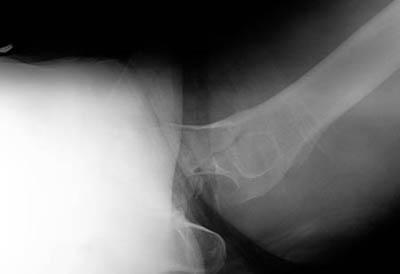

Now look at another radiograph from a different patient. Can you find the fracture?

Click on the image for the answer.

Frog-lateral view of hip